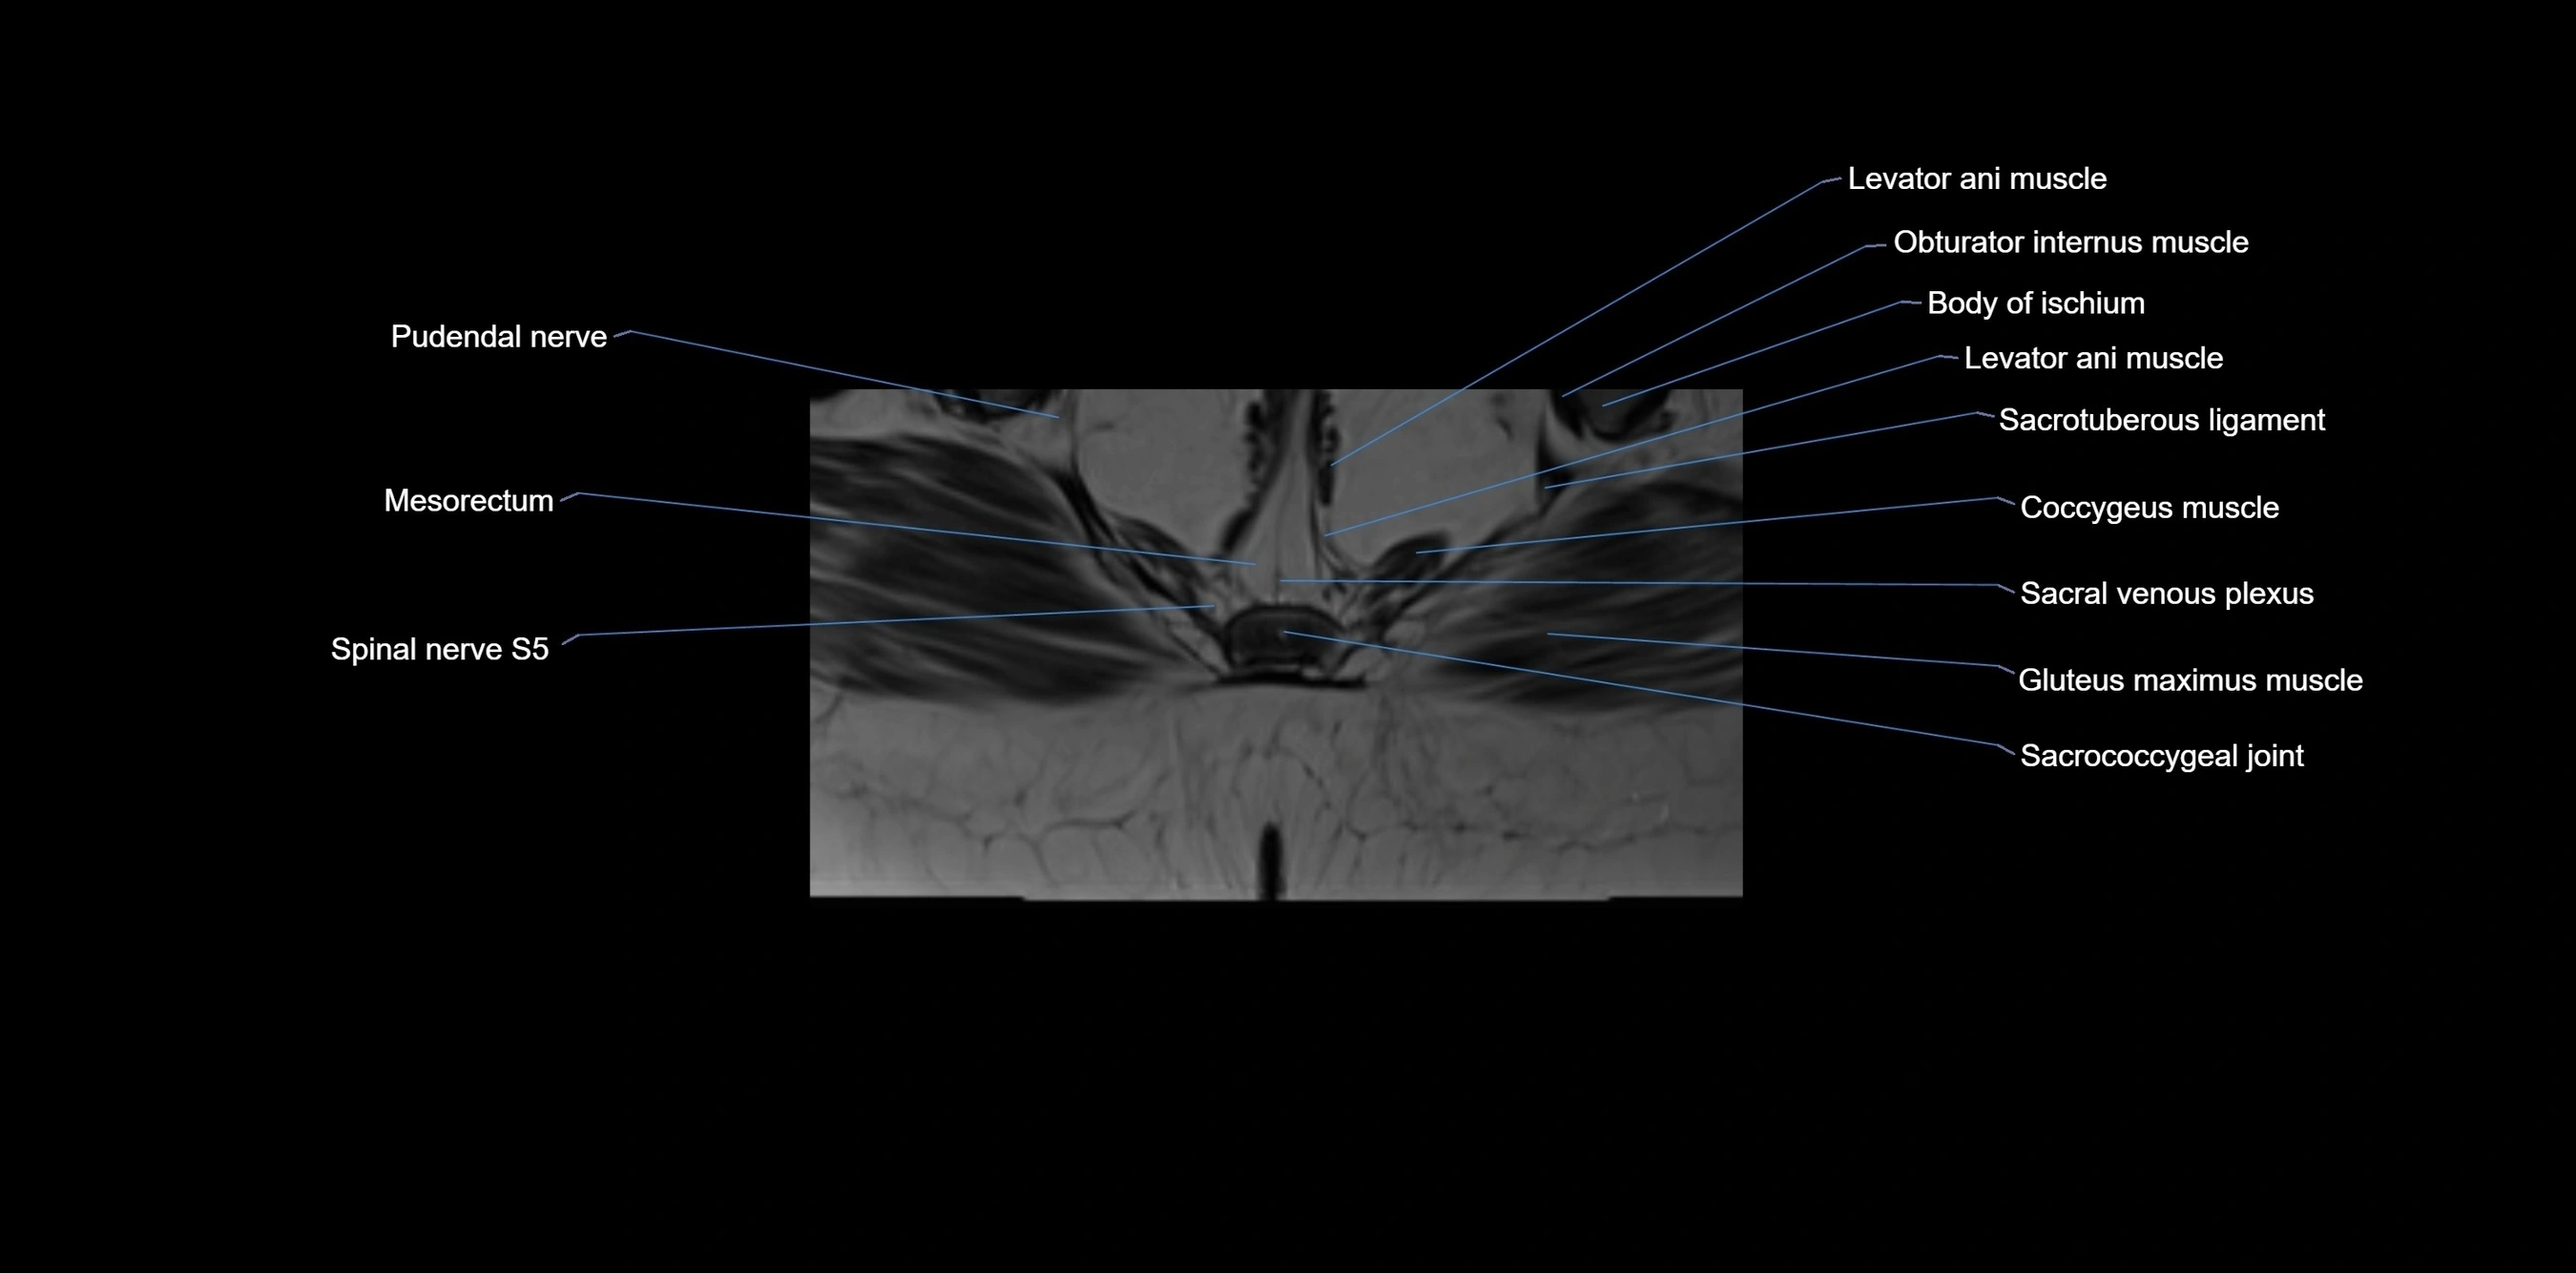

MRI image

image